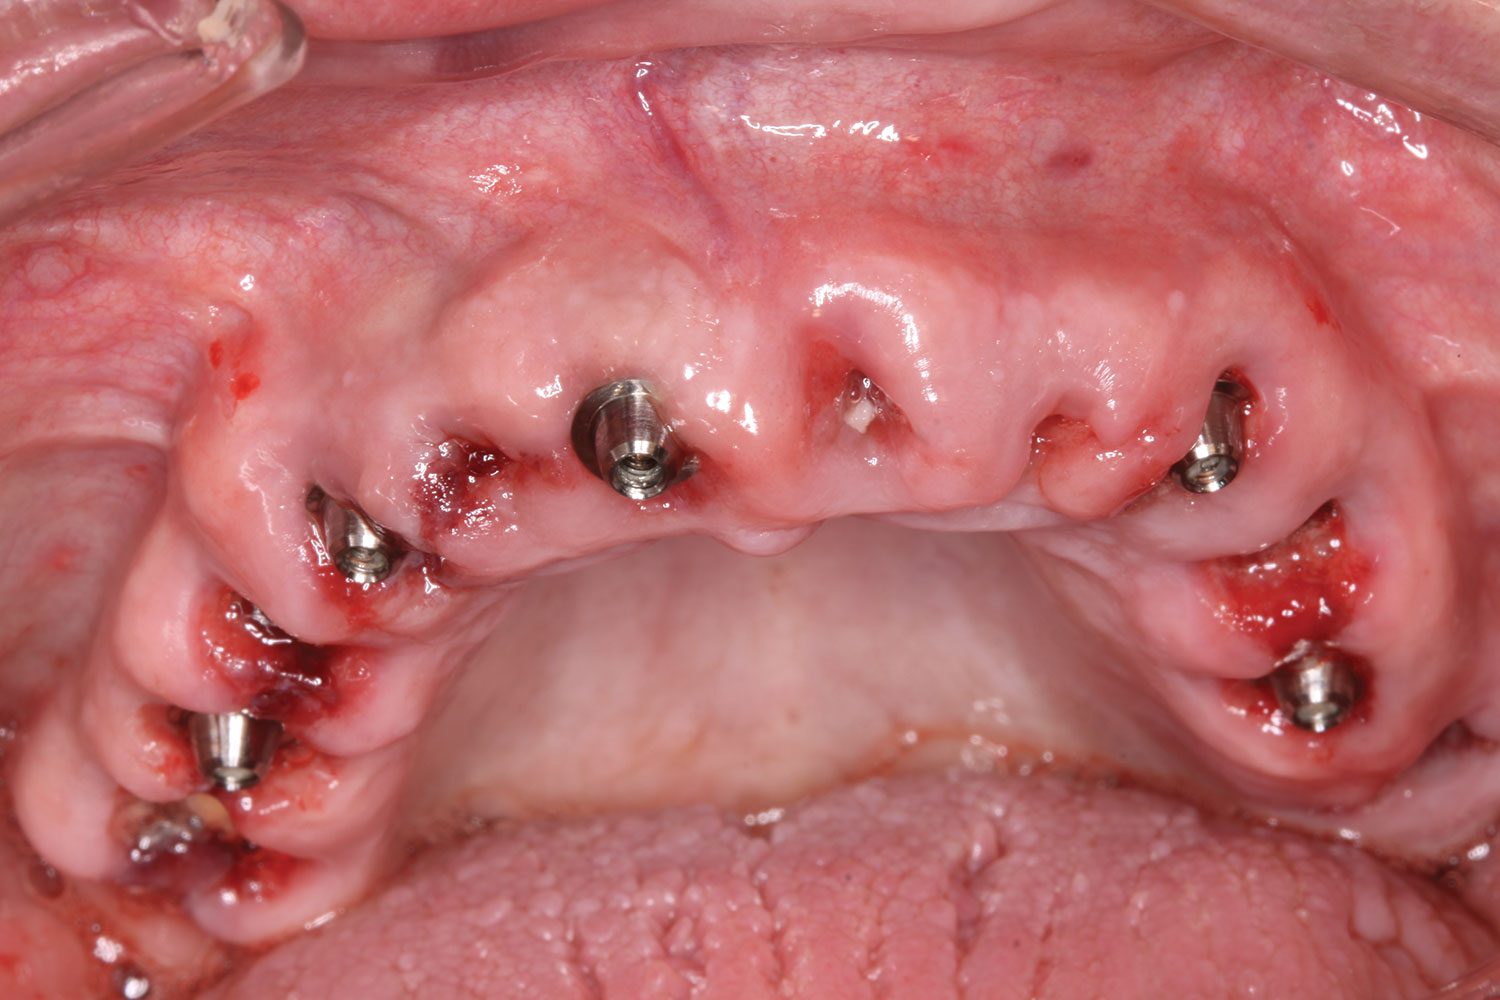

Fig 14. All implants, multi-unit abutments, and scan gauges in place.

Figure 14

Fig 15. Completion of maxillary flapless immediate implant surgery and placement of multi-unit abutments.

Figure 15

A week later the patient presented for surgery for extraction and replacement of her existing maxillary dentition with implants and a screw-retained provisional implant restoration. Teeth Nos. 2, 4, and 6 through 11, 13, and 14 were carefully extracted with attention paid to retaining site dimensions. Immediate implants were inserted into sites Nos. 4, 6, 8, 11, and 13 with high insertion torques in excess of

40 Ncm. Subsequently, multi-unit abutments were placed on all the implants and torqued to 30 Ncm, and scan gauges were placed on implant Nos. 8 and 11 (Figure 12 and Figure 13).

A maxillary intraoral scan was obtained with a digital scanner capturing the two remaining teeth in sites Nos. 5 and 12 and the scan gauges on implants Nos. 8 and 11. Subsequently, teeth Nos. 5 and 12 were extracted. Scan gauges were placed on implants Nos. 4, 6, and 13. At this time, another intraoral scan was captured of all the scan gauges on the five implants with the surrounding soft tissues (Figure 14 and Figure 15).